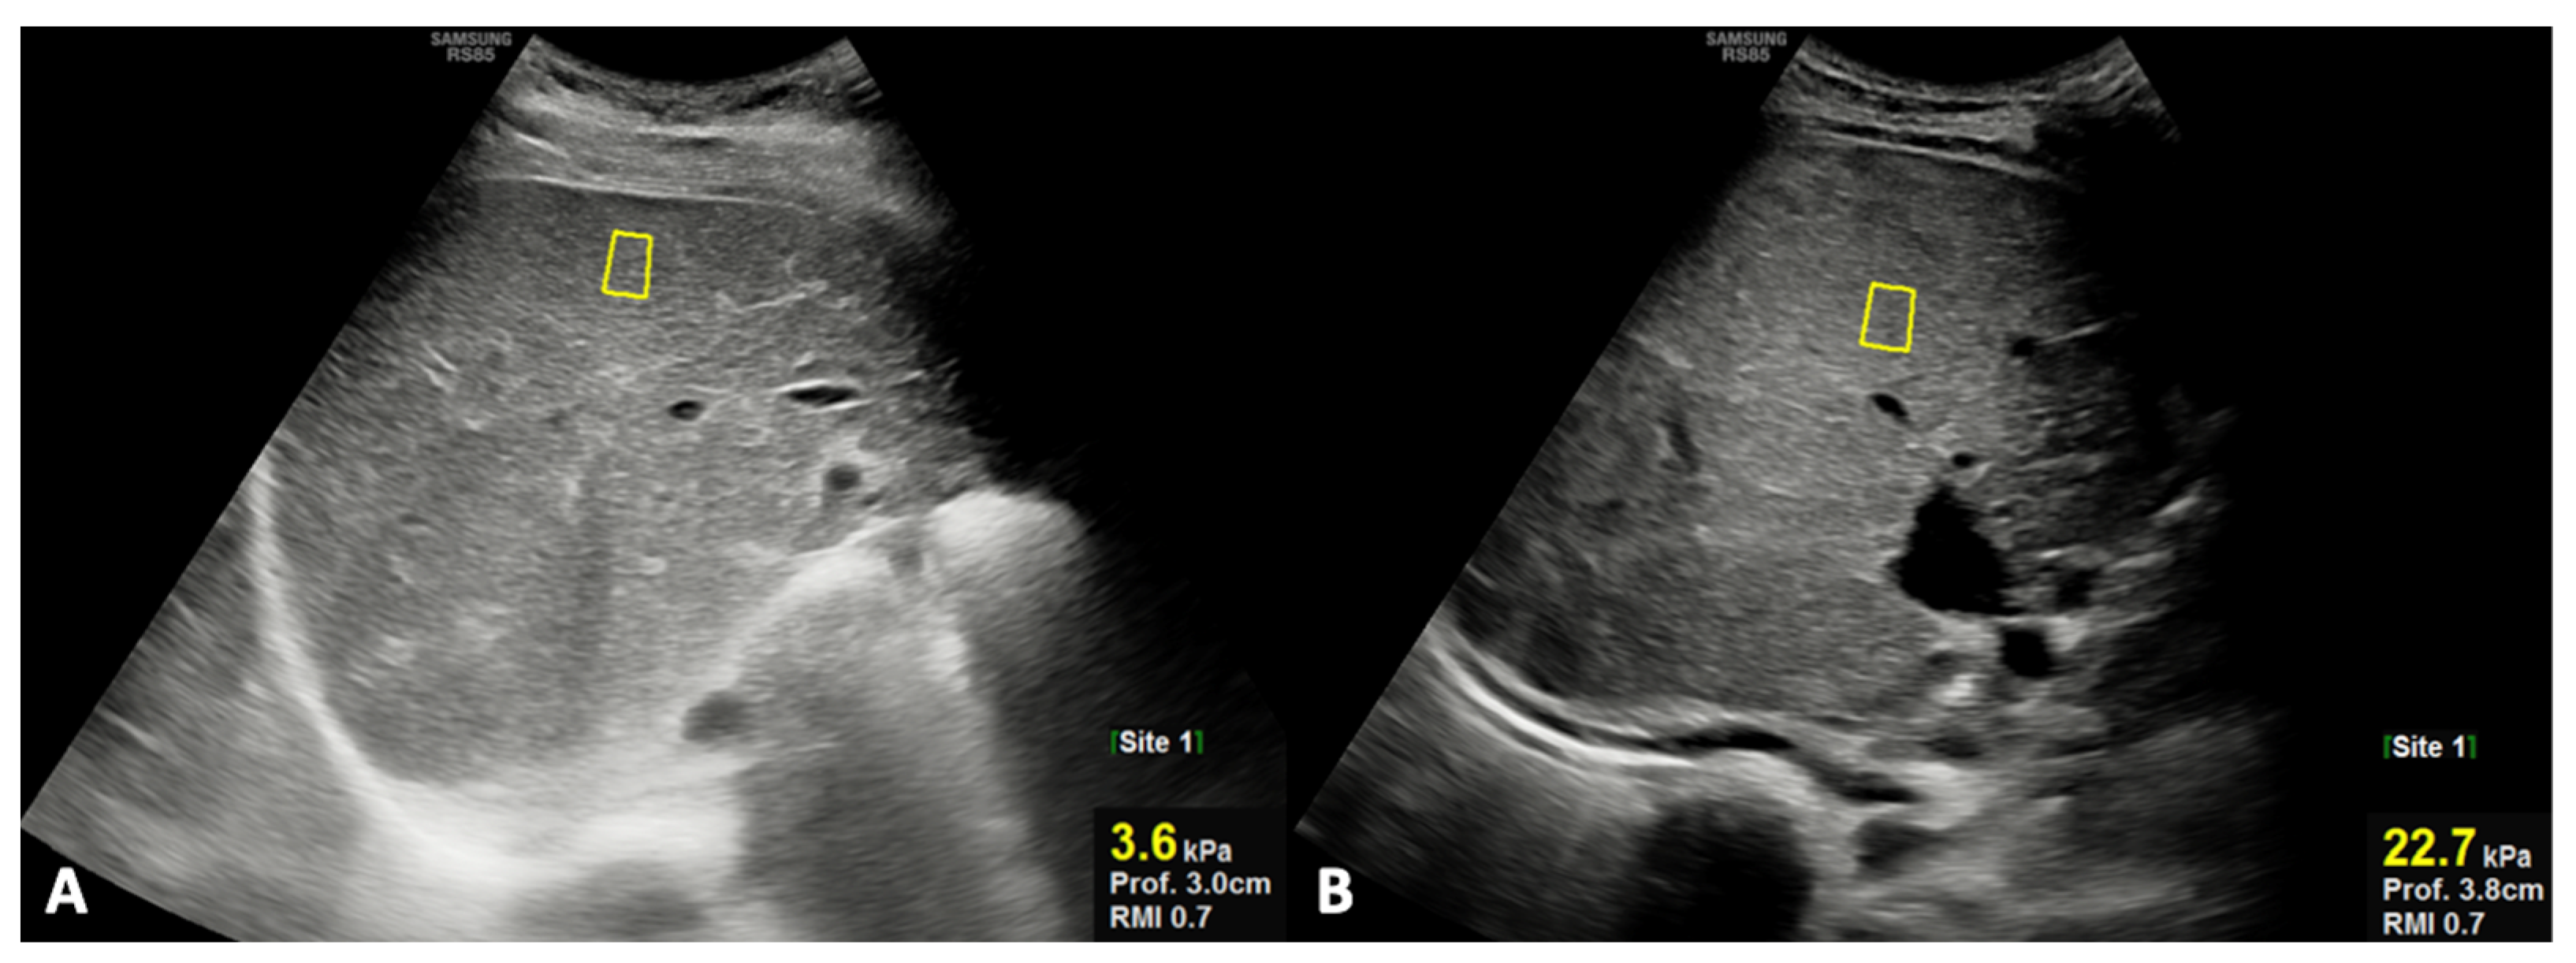

- Caruso, M.; Cuocolo, R.; Di Dato, F.; Mollica, C.; Vallone, G.; Romeo, V.; Petretta, M.; Liuzzi, R.; Mainenti, P.P.; Iorio, R.; et al. Ultrasound, shear-wave elastography, and magnetic resonance imaging in native liver survivor patients with biliary atresia after Kasai portoenterostomy: Correlation with medical outcome after treatment. Acta Radiol. 2020, 61, 1300–1308. [Google Scholar] [CrossRef]

- Caruso, M.; Di Dato, F.; Mollica, C.; Vallone, G.; Romeo, V.; Liuzzi, R.; Mainenti, P.P.; Petretta, M.; Iorio, R.; Brunetti, A.; et al. Imaging prediction with ultrasound and MRI of long-term medical outcome in native liver survivor patients with biliary atresia after kasai portoenterostomy: A pilot study. Abdom. Radiol. 2021, 46, 2595–2603. [Google Scholar] [CrossRef]